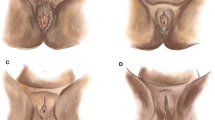

The surgical protocol for clitoral reconstruction involves general anesthesia. Long-acting local anesthesia as well as postoperative topical and oral analgesia is used. The surgical technique described by Foldès [3] is performed, often with modifications: (1) Full thickness mucosal graft from the lateral vaginal wall is transplanted to the clitoral neo-glans to promote faster healing (Fig. 1); (2) fat grafting of the labia majora and above the clitoris is done in case of severe tissue loss and scarring after FGM/C; (3) local skin flaps are used to reconstruct the clitoral hood if there is sufficient adjacent unscarred skin. Mean operation time is 45 min and length of stay 24 h.